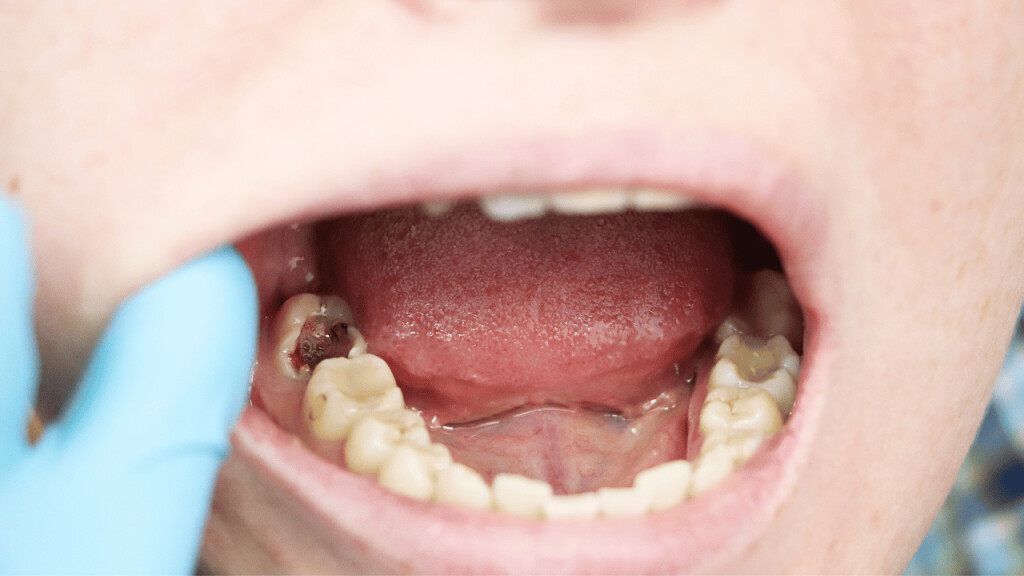

Tooth decay

As tooth decay progresses, it can reach the softer inner layers of the tooth, called dentin and pulp, resulting in sensitivity to hot, cold, or sweet foods and drinks and eventually leading to a toothache. If left untreated, tooth decay can result in an abscess, a painful infection at the root of the tooth that can cause severe pain and swelling. Adhering to your routine dental check-ups, practicing good oral hygiene, and eating a healthy diet can help prevent tooth decay and the resulting toothache.

Abscessed tooth

An abscessed tooth occurs when the pulp inside your tooth becomes infected, typically due to decay or damage. The infection can spread to the tooth’s root and surrounding tissues, causing pain and swelling. In some cases, a pocket of pus may form in the affected area, leading to additional discomfort and even fever. Abscessed teeth may also cause sensitivity to hot or cold foods, a bad taste in your mouth, and difficulty chewing or speaking. If you have an abscessed tooth, inform your provider to prevent further complications and potential tooth loss.